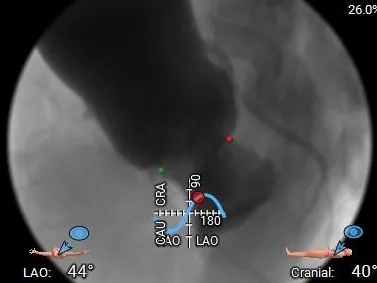

工作体位

双窦展开

左冠切线

手术过程

造影评估:瓣膜位置可,形态稳定

多角度评估,瓣膜位置可

脱钩后造影,瓣膜位置可,几乎无瓣周漏